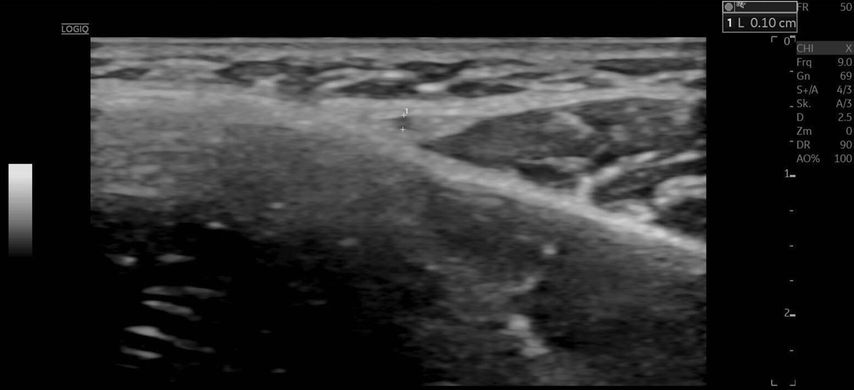

Bei der Erstvorstellung in unserer Praxis zeigten sich eine ausgeprägte Livedo racemosa der Nase sowie ischämische Verfärbungen der linken Wange mit sichtbarer Epidermiolyse. Eine Duplexsonografie ergab eine Hypervaskularisation der Nasenwurzel, ein Hyaluron-Depot sowie Zeichen einer verminderten Mikrovaskularisation («quiet zone») im Bereich der A. angularis.

Die A. facialis imponierte beim Austritt im Bereich des Musculus masseter (oberhalb der Kieferlinie) vasospastisch mit einem maximalen Durchmesser von 1mm. Die abgeleitete systolische Spitzengeschwindigkeit betrug trotz der bestehenden Ischämie 20cm/s, ohne enddiastolische Komponente, was auf eine weitere periphere Vasokonstriktion hindeutete (Abb. 2 und 3).